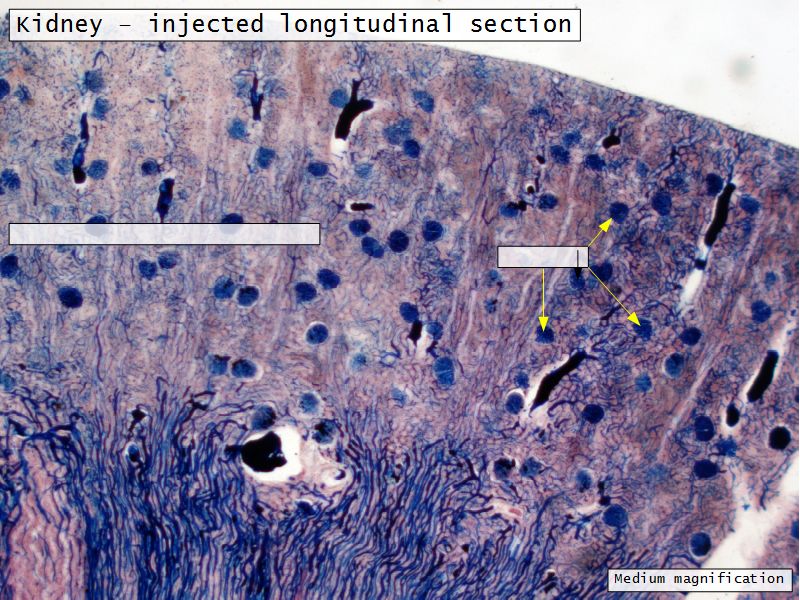

Renal corpuscle

- Tuft of capillaries

- grow into

- Blind end of nephron

- Several layers of epithelium

- Two sides

- Vascular pole

- Tubular pole

Blood flow

- Efferent arteriole

- Smooth muscle in media

- Capillaries

- Fenestrated

- Afferent arteriole

- Smooth muscle in media